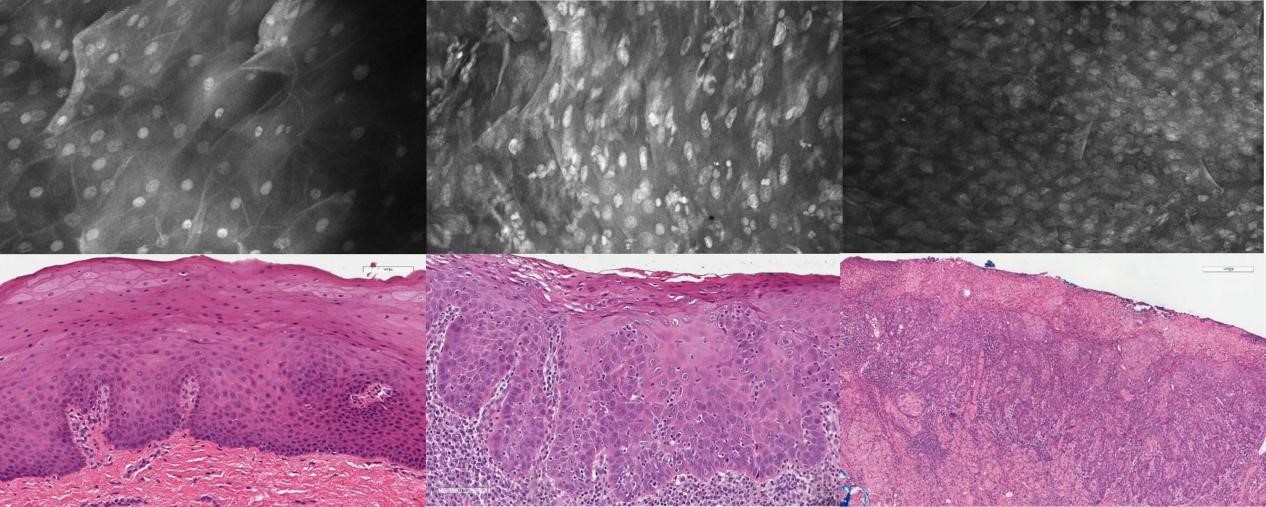

1、口腔癌OptiScan成像

左:正常组;中:癌前期组;右:癌变组。

注:Optiscan技术可以实时捕捉口腔黏膜的亚细胞细节,而无需进行活组织检查。Scale bar=100μm。